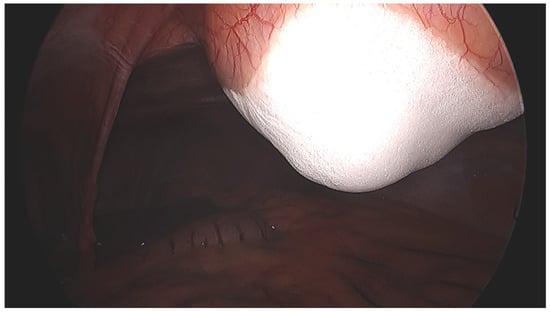

2.2. Procedure and Technique